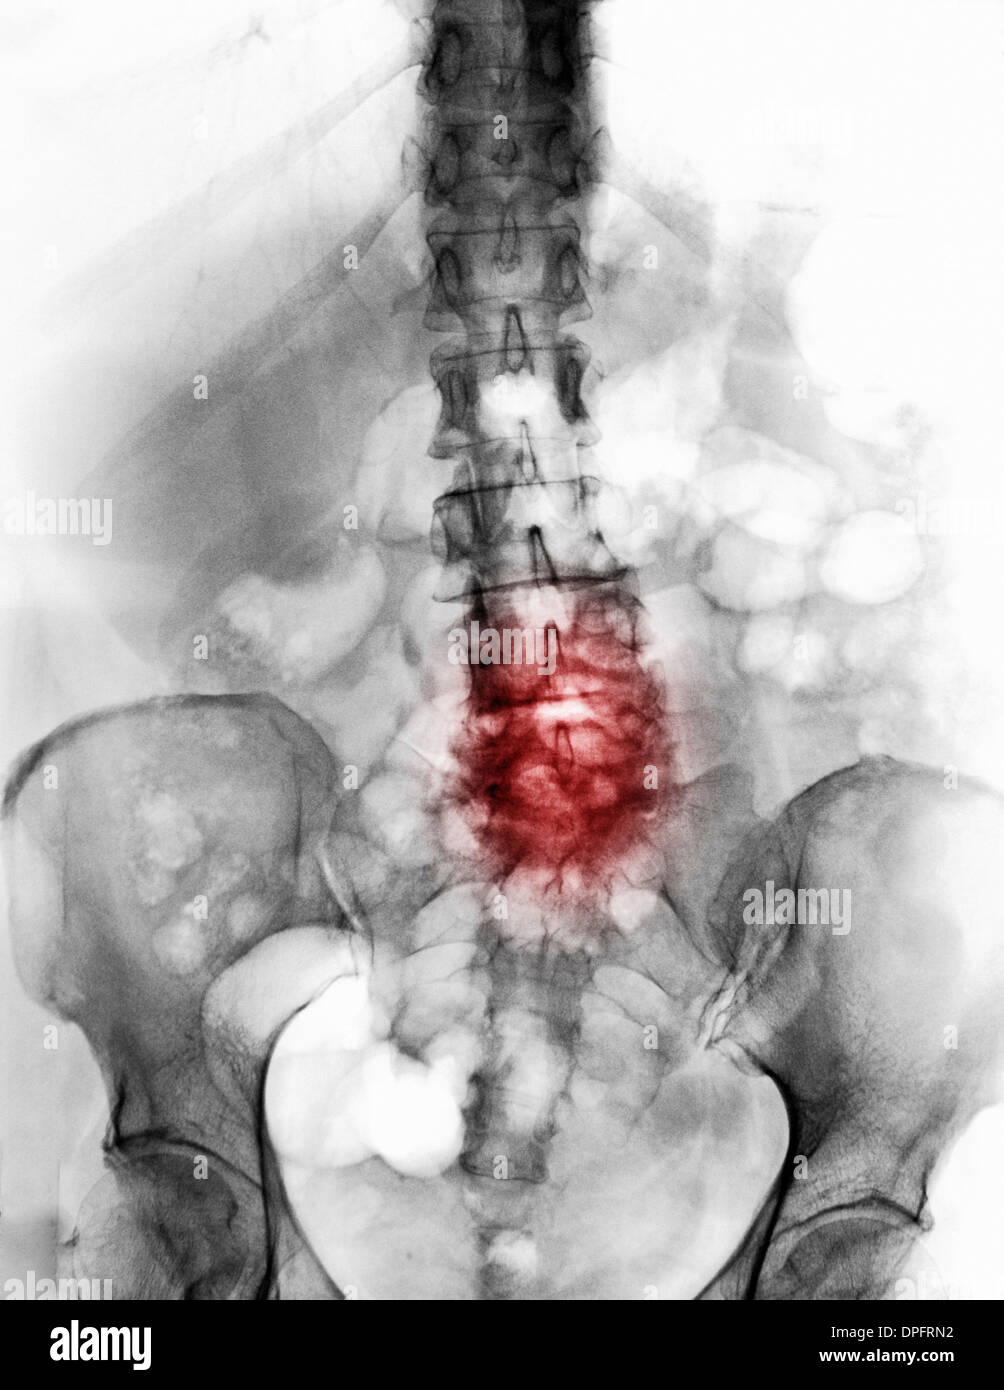

spine x-ray with degenerative arthritic changes Stock Photohttps://www.alamy.com/image-license-details/?v=1https://www.alamy.com/spine-x-ray-with-degenerative-arthritic-changes-image65501438.html

spine x-ray with degenerative arthritic changes Stock Photohttps://www.alamy.com/image-license-details/?v=1https://www.alamy.com/spine-x-ray-with-degenerative-arthritic-changes-image65501438.htmlRFDPFRN2–spine x-ray with degenerative arthritic changes